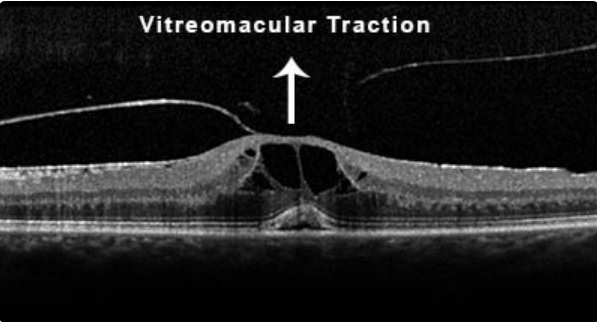

O que é a Síndrome de Tração Vítreomacular?

Qual é o quadro clínico apresentando pelos pacientes com STVM?

Edema Cistóide

Descolamento da fóvea

Buracos lamelares

Qual é a classificação da STVM?

Adesão Vítreomacular: sem distorção da arquitetura macular

STVM Focal: adesão menor 1500 micrômetros

STVM Difusa: adesão maior 1500 micrômetros